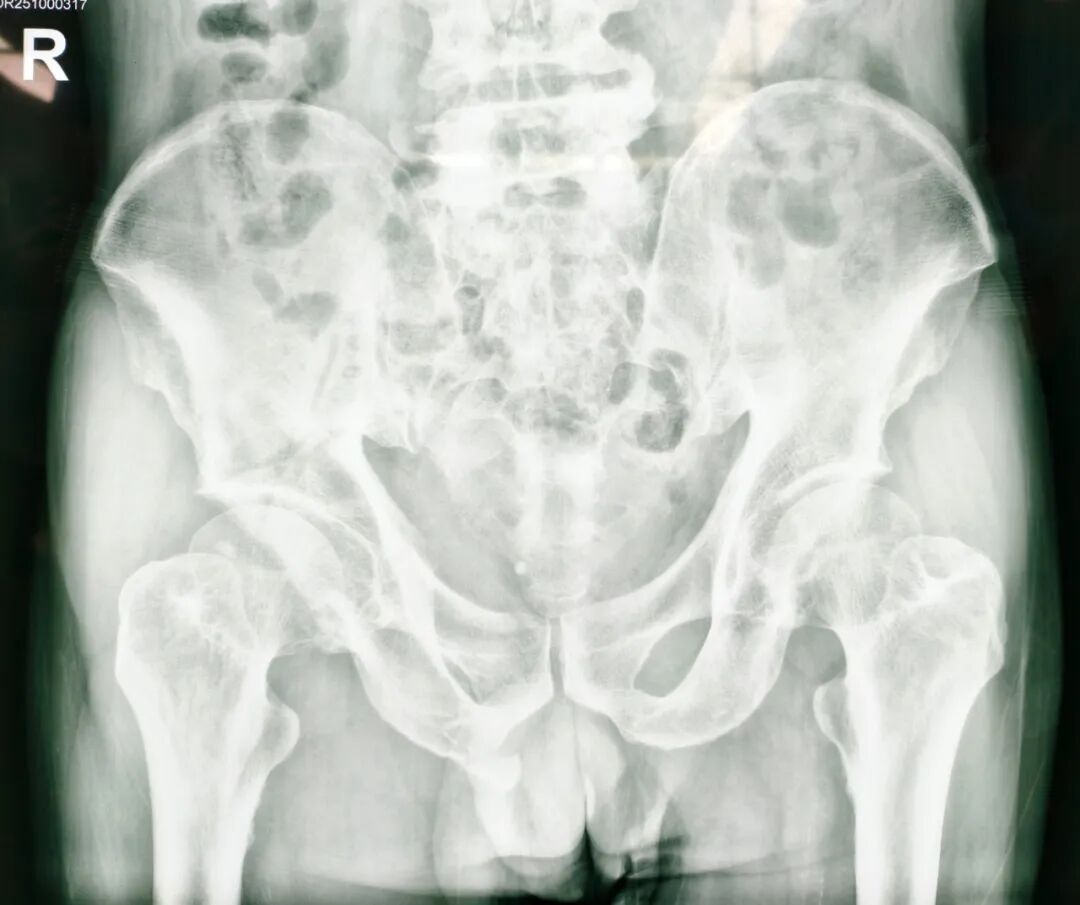

此次接受手术的七旬老人,因干活时不慎从自驾车摔落,导致全身多部位骨折,其中包括胸椎压缩性骨折、腰椎压缩性骨折、髂骨骨折、骶骨骨折、尾骨骨折、耻骨骨折、坐骨骨折。因骨盆结构复杂、周围血管神经密集,骨盆骨折素有“创伤之王”之称。面对患者骨盆多处骨折、血红蛋白偏低、传统手术可能带来较大创伤和出血风险等难题,贾长军主任团队果断选择借助最新引进的骨科手术机器人,制定个性化微创手术方案。

术前

团队通过三维影像重建,为患者量身定制手术路径,数据导入系统后生成个性化复位方案。